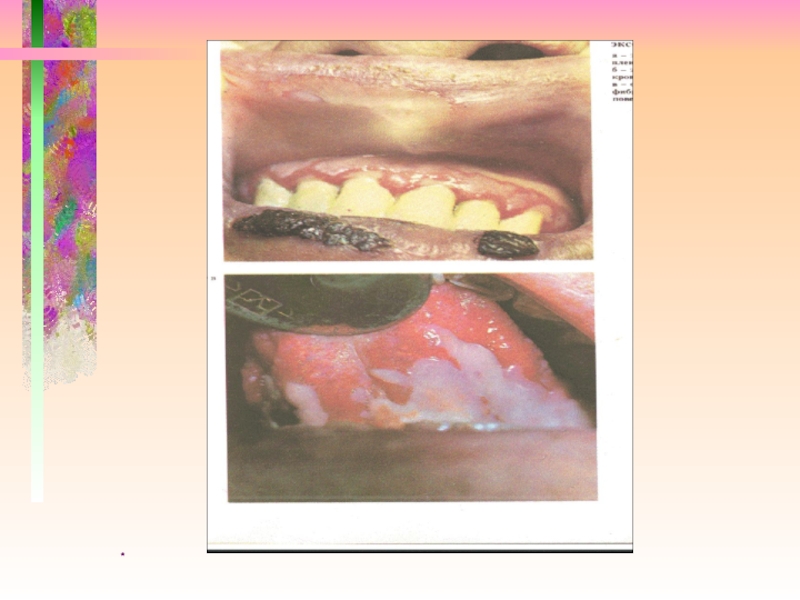

Многоформная экссудативная эритема

Полиморфизм высыпаний

пятна -эритема

папулы

волдыри

пузыри

пузырьки

корки (геморрагические)

Локализация в полости рта

губы

дно

полости рта

щеки

небо

На коже-”кокарды”

тыльные поверхности кистей, стоп, предплечье, голени